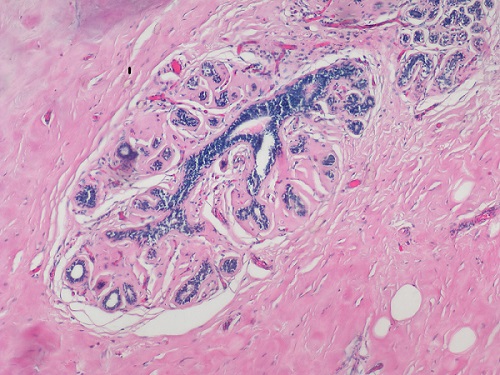

常用的染色方法是苏木素-伊红(Hematoxylin-Eosin)染色法,简称H.E染色法。这种方法对任何固定液固定的组织和应用各种包埋法的切片均可使用。苏木素是一种碱性染料,可使组织中的嗜碱性物质染成蓝色,如细胞核中的染色质等;伊红是一种酸性染料,可使组织中的嗜酸性物质染成红色,如多数细胞的胞质、核仁等在H.E染色的切片中均呈红色。

(明美生物显微镜搭配msx2拍摄HE染色的乳腺癌病理切片,红色为胞质,蓝色为染色体)